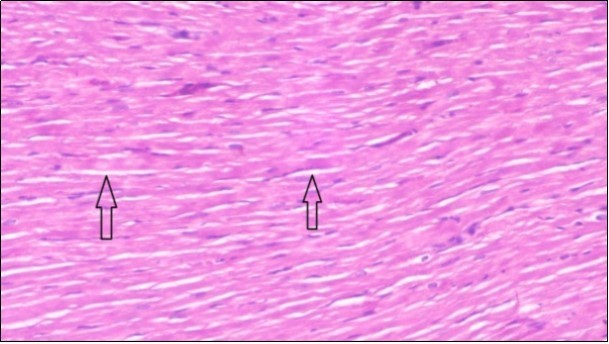

An important organ that is affected directly by the obesity which is the heart: The heart is the main important organ in circulatory system, the heart wall has three basic layers; the tunica intima of the heart is called endocardium, the tunica media of the heart is called the myocardium, the tunica adventitia of the heart the epicardium. The histological examination of the hearts of control rats feeding standard diet showing normal cardiac tissue with elongated, unbranched multinucleated muscle fibers (arrow), (Figure 1). The rats are feeding (HFD) for 2 weeks (obese rats) showing large number of inflammatory cells (star), degeneration muscles fiber ,circle and congested Blood vessels (arrow) (Figure 2). By comparison hearts of rats are treated by fennel after obesity and control rats observed show improved cardiac tissue with less infiltration (star) and well organized elongated muscle fibers with peripheral nuclei (arrow) (Figure 3). While examination of rats heart that treated by ator after obesity appears show less improved cardiac tissue with few inflammatory cells between disorganized muscle fiber (star), (Figure 4). While combined hearts of rats are treated by fennel and ator after obesity and control mice are showing nearly cardiac tissue with well-organized muscles fibers (arrow), (Figure 5).

Figure 5.Photomicrogragh of heart section of treated rat with both fennel herb and Ator drug showing nearly normal cardiac tissue with well-organized muscles fibers (arrow), (H&E) (400X).

Photomicrogragh of heart section of treated rat with both fennel herb and Ator drug showing nearly normal cardiac tissue with well-organized  muscles fibers (arrow), (H&E) (400X).